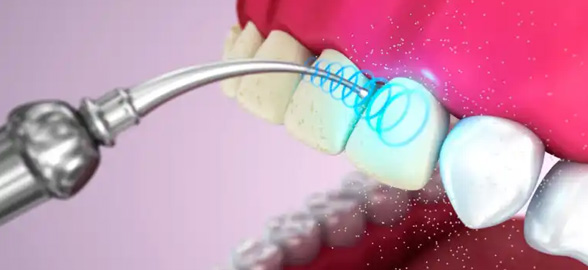

En la odontología moderna, las puntas de ultrasonido han revolucionado la forma en que se abordan los tratamientos dentales.